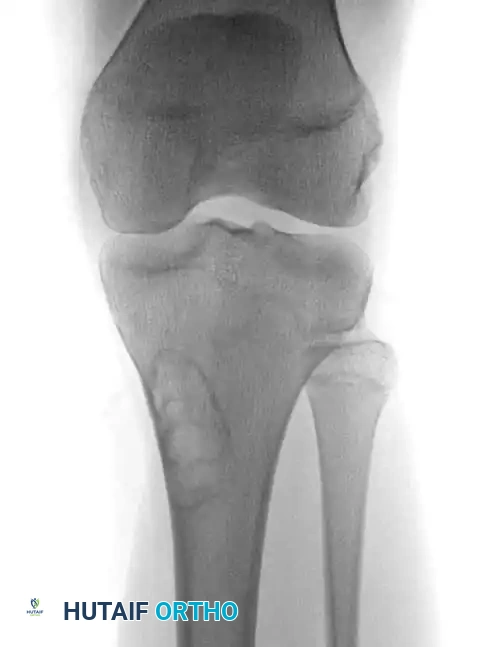

On plain radiography, an NOF presents as a well-defined, lobulated, and eccentrically located radiolucency within the metaphysis.

Fig. 20-8 A and B: Anteroposterior and lateral radiographs demonstrating a classic nonossifying fibroma of the proximal tibia in a 15-year-old patient. Note the eccentric location and sclerotic margins.

A multilocular appearance with distinct ridges in the bony wall, sclerotic scalloped borders, and focal erosion of the inner cortex are hallmark findings. Crucially, there is an absolute absence of periosteal reaction unless a pathological fracture has occurred.